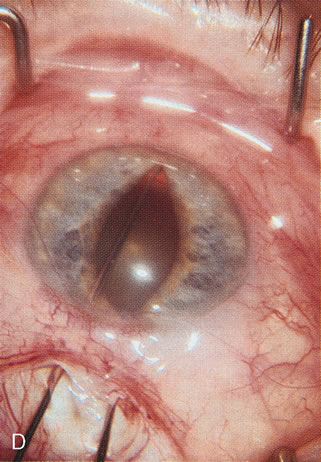

Fig. 3. Partial bleb failure following clear corneal phacoemulsification with foldable IOL. A. Preoperative bleb appearance prior to temporal lens extraction. Preoperative IOP was 12 mm Hg on no antiglaucoma medications. Time from 5-FU trabeculectomy surgery to lens extraction was one year. B. Bleb appearance 2 months after clear corneal cataract surgery with topical anesthesia. Following lens extraction, increased vascularity was noted along with decreased size of the filtering bleb. IOP increased to 20 mm Hg as early as 2 weeks after surgery, necessitating topical antiglaucoma therapy. C. High magnification view of bleb before lens extraction demonstrates diffuse pale bleb. D. High magnification view of bleb 2 months after surgery. There are vessels surrounding the nasal side of the bleb and the overall bleb size is smaller.

Fig. 1. The anatomic advantage of small incision cataract surgery for the glaucoma patient. A. Long-term bleb function with a large cataract incision is difficult to achieve with either ECCE-trabeculectomy or trabeculectomy followed later by ECCE. This bleb failed to form sufficiently when combined with large incision ECCE. The inflammation, bleeding, and long-term wound healing with stimulation of fibroblasts associated with this technique are more likely to cause bleb failure. In addition, the increased iris manipulation necessary to deliver the nucleus and subsequent iris repair adds to the long-term breakdown of the blood aqueous barrier. B and C. Two-site phacotrabeculectomy has the advantage of small incision cataract surgery combined with separate site trabeculectomy. The incision size is one third the size of the standard ECCE. The inflammation is less severe, and cataract wound healing is confined to the temporal area. Visual rehabilitation with phacoemulsification and foldable IOL is much faster. Phacoemulsification allows successful lens extraction even in the unfriendly environment of a smaller pupil compared with ECCE. The trabeculectomy is performed in an entirely different site, well away from the wound healing associated with temporal phacoemulsification. The likelihood of this filter functioning long-term is greater than with ECCE-trabeculectomy. D. The surgeon also has the option of single-site phacotrabeculectomy with foldable IOL. Both the lens extraction and trabeculectomy are performed through one small 3.5-mm limbal incision.